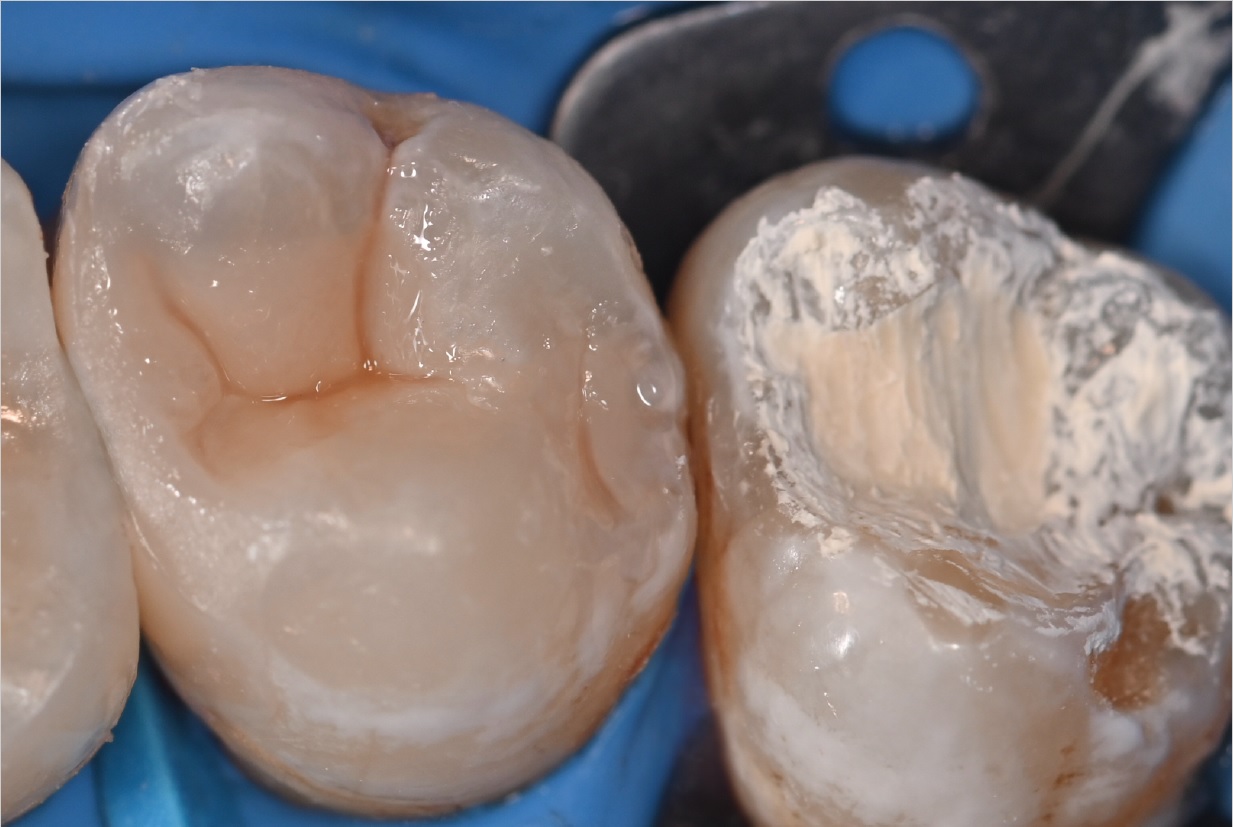

Εικ. 1: Ασθενής 21 ετών προσήλθε στην κλινική με ευαισθησία στο κρύο στο άνω δεξιό τεταρτημόριο. Η ενδοστοματική κλινική εξέταση αποκάλυψε μια παλιά, αποκατάσταση σύνθετης ρητίνης στον δεύτερο άνω γομφίο με ρωγμές και τερηδόνα στον τρίτο γομφίο. Η ακτινογραφία επιβεβαίωσε μια βαθιά τερηδονική αλλοίωση στον τρίτο γομφίο και την παρουσία μιας κατεστραμμένης αποκατάστασης σύνθετης ρητίνης στον δεύτερο γομφίο.

Εικ. 2: Η σωστή εφαρμογή του ελαστικού απομονωτήρα και η εξακρίβωση της πλήρους απομόνωσης είναι απαραίτητες πριν από τη διάνοιξη της κοιλότητας για την αποφυγή περαιτέρω μόλυνσης, ιδιαίτερα σε περιπτώσεις άμεσης ή έμμεσης επικάλυψης του πολφού.

Εικ. 3: Μετά την αφαίρεση της προηγούμενης αποκατάστασης σύνθετης ρητίνης και τον καθαρισμό της τερηδονισμένης αλλοίωσης στον τρίτο γομφίο, παρατηρήθηκε μια βαθιά κοιλότητα κοντά στον πολφό. Και στις δύο περιπτώσεις, αποφασίστηκε η εφαρμογή του Biodentine XP χρησιμοποιώντας μια τεχνική biobulk-fill για την έμμεση κάλυψη του πολφού, με σκοπό την αποκατάστασης της οδοντίνης, την παροχή ενός προστατευτικού φραγμού και τη διατήρηση της ζωτικότητας του δοντιού.